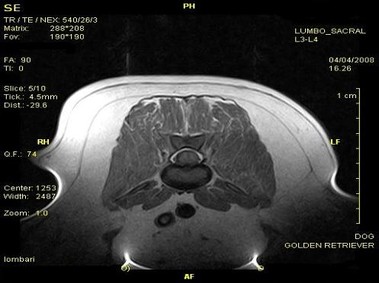

В настоящее время МРТ является наиболее предпочтительным методом визуализации любых мягких тканей, особенно для визуализации травм и патологий центральной нервной системы и суставов. Особенности Vet-MR позволяют использовать данный метод визуализации также в сфере ветеринарии.

Vet-MR специально разработана для визуализации небольших животных и является результатом внимания к деталям при разработке магнита, катушки и электронных компонентов, обеспечивая высокое качество экономически эффективной и простой в использовании МРТ в сфере ветеринарии.

- Высокое качество изображения

- Специальное программное обеспечение, полный набор предварительно установленных последовательностей и протоколов для ветеринарных целей